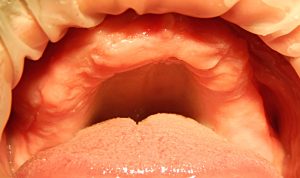

Клиническая картина. При полной потере зубов зависит от причины, вызвавшей потерю зубов, времени, прошедшего с момента их удаления, возраста пациента, его общего состояния и многих других причин. Ведущими симптомами являются атрофия альвеолярного отростка, развитие старческой прогении, потеря фиксированной межальвеолярной высоты, изменение внешнего вида больного и нарушение функции жевания и речи.

Лечение складывается из обследования, установления типа челюсти, предварительной подготовки полости рта (по показаниям), снятия ориентировочного, а затем функционального оттисков, определения центрального соотношения челюстей, проверки конструкции протеза, наложения протеза и контроля за привыканием больного к нему.

Предварительная специальная подготовка больного заключается в проведении мероприятий, облегчающих ортопедические процедуры или создающих условия для лучшей фиксации и стабилизации протеза. К первым относится, например, ликвидация микростомии, ко вторым — пластика альвеолярного отростка для повышения его высоты, углубление преддверия полости рта, устранение рубцовых тяжей, уродующих переходную складку, перенесение места прикрепления уздечек, удаление небного торуса, экзостозов, костных выступов на протезном ложе, мешающих протезированию, и др.

Клиническими тестами для оценки успешности протезирования пациентов с беззубыми челюстями являются восстановление внешнего вида больного (восстановление правильных очертаний губ, их линии смыкания, носогубных складок, восстановление высоты нижней трети лица), фиксация и стабилизация протезов, характер разжевываемой пищи, состояние тканей протезного ложа, четкость речи и отсутствие усталости в мышцах языка после длительного разговора.